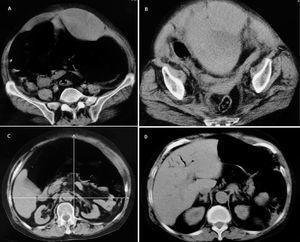

Se trata de un hombre de 73 años, tratado con antidiabéticos orales que acudió a un hospital comarcal por dolor abdominal de dos días de duración. La detección de una hiperamilasemia de 2.303 U/l llevó al diagnóstico de pancreatitis aguda y el paciente fue tratado con reposo intestinal, fluidos e imipenem. Un día más tarde, el paciente fue intubado orotraquealmente y trasladado a la UCI debido a disnea, hipotensión arterial, oliguria y hemorragia por sonda nasogástrica. Antes del traslado, una TC abdominal con contraste (fig. 2) reveló un área de hipoperfusión junto a la cabeza del páncreas (sugestiva de pancreatitis necrotizante), una gran cantidad de gas mesentérico y peripancreático, neumatosis intestinal, gas venoso portal intrahepático, infartos hepáticos y un nivel aire-contraste radiológico en la vena porta.

Figura 2. Tomografía computarizada abdominal con contraste que muestra gas venoso portal localizado en la periferia del hígado asociado con infartos hepáticos (A) y una zona de hipoperfusión en el cuerpo proximal del páncreas rodeada de aire peripancreático (flechas blancas) y un nivel de aire-material de contraste en la vena porta (flecha negra) (B).